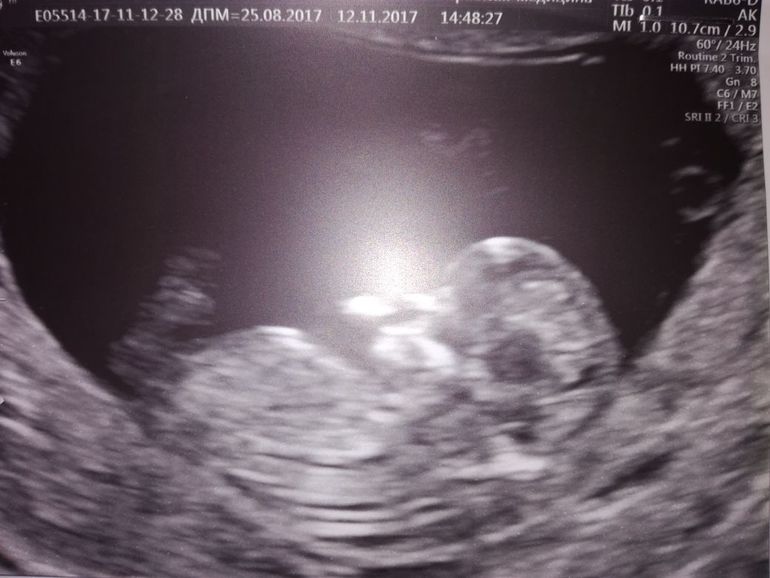

УЗИ, КТГ, доплерКакой сегодня волнительный день , свои // я впервые увидела 15.09 и мне кажется эти два месяца ожидания скрининга-были вечностью. Хорошо, что у Инвитро есть возможность послушать сердцебиение за 150 р и я бегала периодически на свидания с малышом, просто не могла по-другому держать себя в руках. Этот вечный мондраж и трясучка. Сегодня ровно 11+2, мы поехали с мужем на платный скрининг, на 3д УЗИ к Пятых. Это конечно что-то потрясающее, огромный экран, где видно каждый пальчик. Предстоит еще и бесплатный скрининг в 13 недель, от него не отвертеться, но там не пускают мужа, не дают фото, поэтому мы сделали свой собственный скрининг чуть-чуть пораньше. Малыш уже настоящий маленький человечек! Сначала он спал и прикрывал носик рукой, но потом его разбудили и он начал так активно танцевать в животе, это непередаваемые ощущения, он там внутри живой, такой родной и долгожданный!

Результат крови будет завтра. Надеюсь там все хорошо.Пугает низкая плацентация. У кого так было и чем это грозит? Врач сказала про половой покой, но мы итак ни-ни с тех пор как увидели //. Сердечко 170 ударов в минуту, нормально на этом сроке или быстро? Мне кажется к 1 скринингу должно чуть меньше становиться, хотя наверное все индивидуально. Ну и что касается пола... Сначала Пятых уверенно сказала, что бугорок торчит на мальчика, но потом забрала свои слова обратно и сказала, что все- таки еще рановато. Может кто-то разглядит на узи что там у нашего малыша)))?